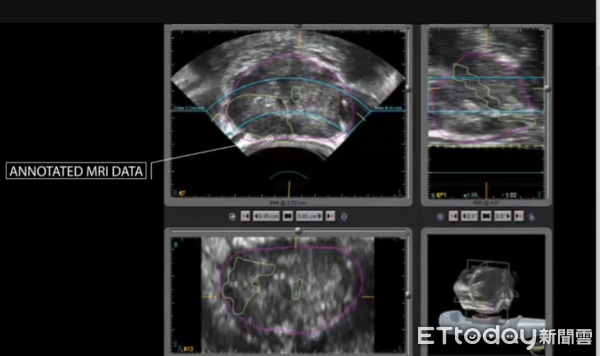

除了技術上的優勢,屏基此次引進的「海福刀」系統更搭載人工智慧(AI)導航與影像融合技術,能準確辨識腫瘤位置與範圍,避免傷及周邊健康組織,進一步提高治療精準度與安全性。